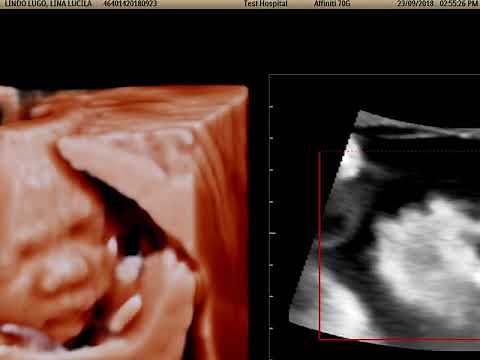

Fetal Heart Navigator (FHN). Epiq 5G. Philips.

已浏览 681 次

2018年9月26日

YouTube

Carlos Lopez Casanas